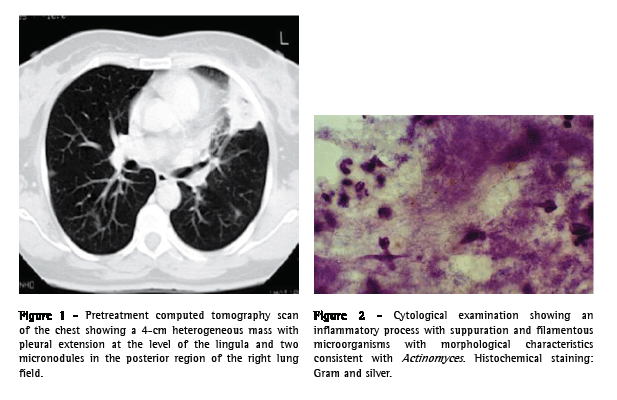

A 55-year-old Caucasian female, a secretary and a nonsmoker, sought treatment in the emergency room. The patient had a history of chronic hepatitis B, arterial hypertension, mixed dyslipidemia, and multiple untreated dental caries. She reported a three-week history of daily diarrhea, heartburn, retrosternal discomfort that was aggravated in the supine position, asthenia, anorexia, and weight loss (5 kg). One week after the onset of symptoms, the patient presented progressively worsening chest pain (on the left side) with pleuritic characteristics, frequent fits of dry cough upon exertion, and an isolated peak of fever had appeared. The electrocardiogram results were normal, and endoscopy of the upper digestive tract revealed a compliant cardia and antral gastritis. A chest X-ray showed a heterogeneous hypotransparency, with loss of substance in its center, in the middle third of the left lung field. A computed tomography scan of the chest revealed a 4-cm mass with heterogeneous content and pleural extension to the level of the lingula, as well as two micronodules in the posterior region of the right lung field (Figure 1). An etiological study was carried out based on the working diagnosis of pulmonary neoplasia.

From the analytical study, we highlight the following results: an erythrocyte sedimentation rate of 98 mm in the first hour; a cancer antigen 125 level of 63.3 U.mL-1 (<35.0); a carcinoembryonic antigen level of 3.55 ng.mL-1 (<2.5); and a slight increase in the C-reactive protein level. The serum immunological study, the viral marker analysis, and the final analytical study revealed no other significant alterations. The results of colonoscopy, transabdominal pelvic ultrasound, mammography, and cervicovaginal cytology were normal. The first fiberoptic bronchoscopy performed showed diffused signs of inflammation at the level of the lingula. The cytological examinations of aspirate, bronchial lavage, and bronchoalveolar lavage were negative for neoplastic cells. Microbiological analysis under anaerobic conditions also yielded negative results, as did testing for acid-fast bacilli. The patient was then submitted to transthoracic needle aspiration biopsy (TNAB), which, in the extemporaneous cytological examination, showed an inflammatory process with suppuration. In view of this provisional result, antibiotic therapy with oral levofloxacin 500 mg daily was initiated, and it was decided that a second fiberoptic bronchoscopy should be carried out. However, the cytological examination of the TNAB revealed morphological aspects consistent with the presence of Actinomyces, confirmed through microbiological culture analysis of the bronchial and bronchoalveolar lavage of the second fiberoptic bronchoscopy, in which A. naeslundii was identified (Figure 2). Testing for acid-fast bacilli yielded negative results. Due to the clinical and radiological improvement after a month of treatment (Figure 3), we opted to maintain the antibiotic therapy already initiated, altering the dose schedule: intravenous levofloxacin (500 mg/day) for four weeks and oral levofloxacin (500 mg/day) thereafter. There were no adverse drug effects, and the treatment was continued for 16 weeks, until there was complete radiological normalization. Analytically, we observed a decrease in the erythrocyte sedimentation rate and in the initially altered levels of both tumor markers, as well as normalization of the C-reactive protein level. The patient was also submitted to dental treatment.